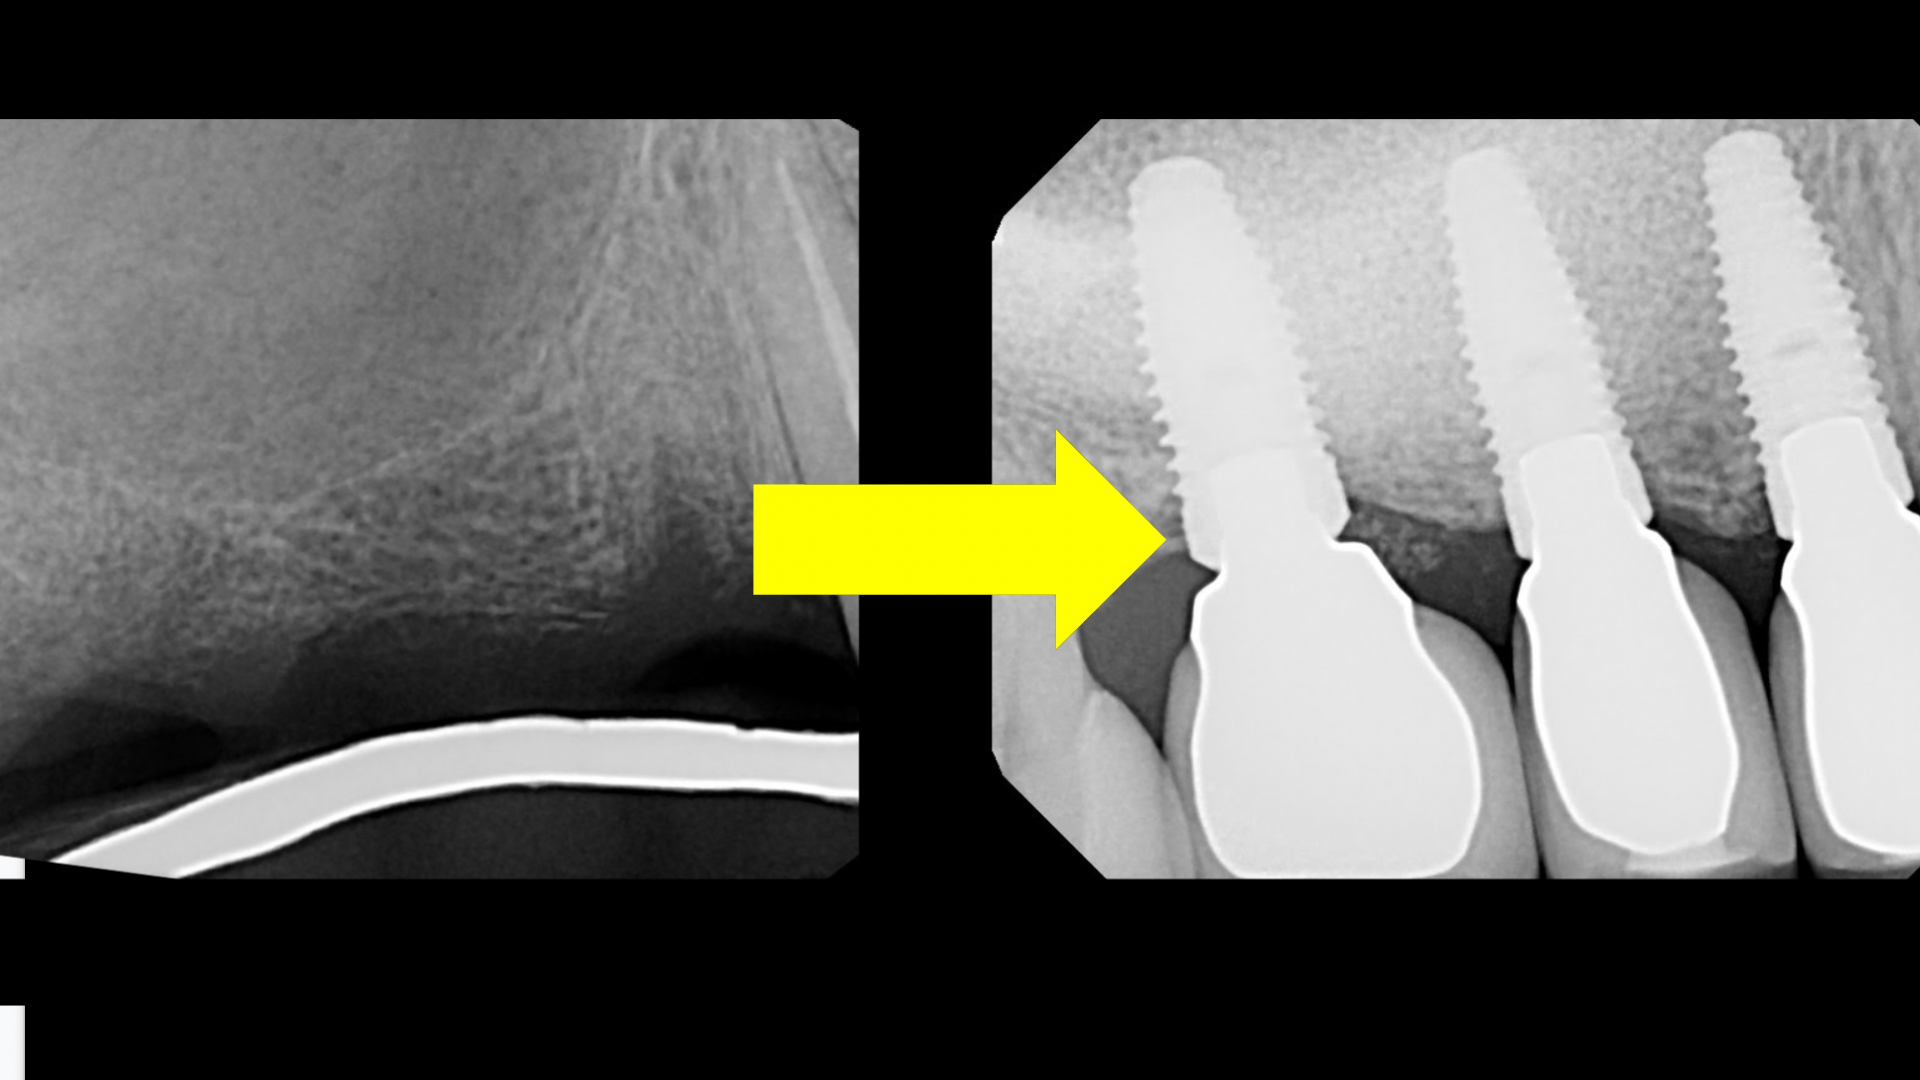

HOW TO SINUS LIFT &

PLACE IMPLANTS

WITH CLARITY & SAFETY

Learn the 10 reasons why dentists fail in sinus lifting, how to avoid them, how to find simple and predictable sinus lifts, and much more.

In this free training, World-Renown Beverly Hills periodontist, Dr. Ziv Simon, will share his step-by-step roadmap to prepare the posterior maxilla for implants with simple sinus lift surgery.